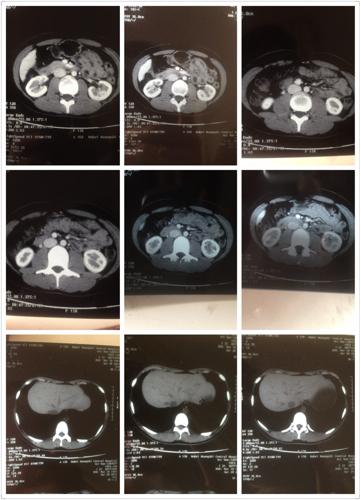

肝囊肿ct图片报告,肝囊肿ct图片

要求给予治疗,从ct检查来看,肝内多发囊肿,最大者左右肝各一12cm直径

肝囊肿 和 甘油三酯 高

请医生帮我看看片,是肝血管瘤肝囊肿还